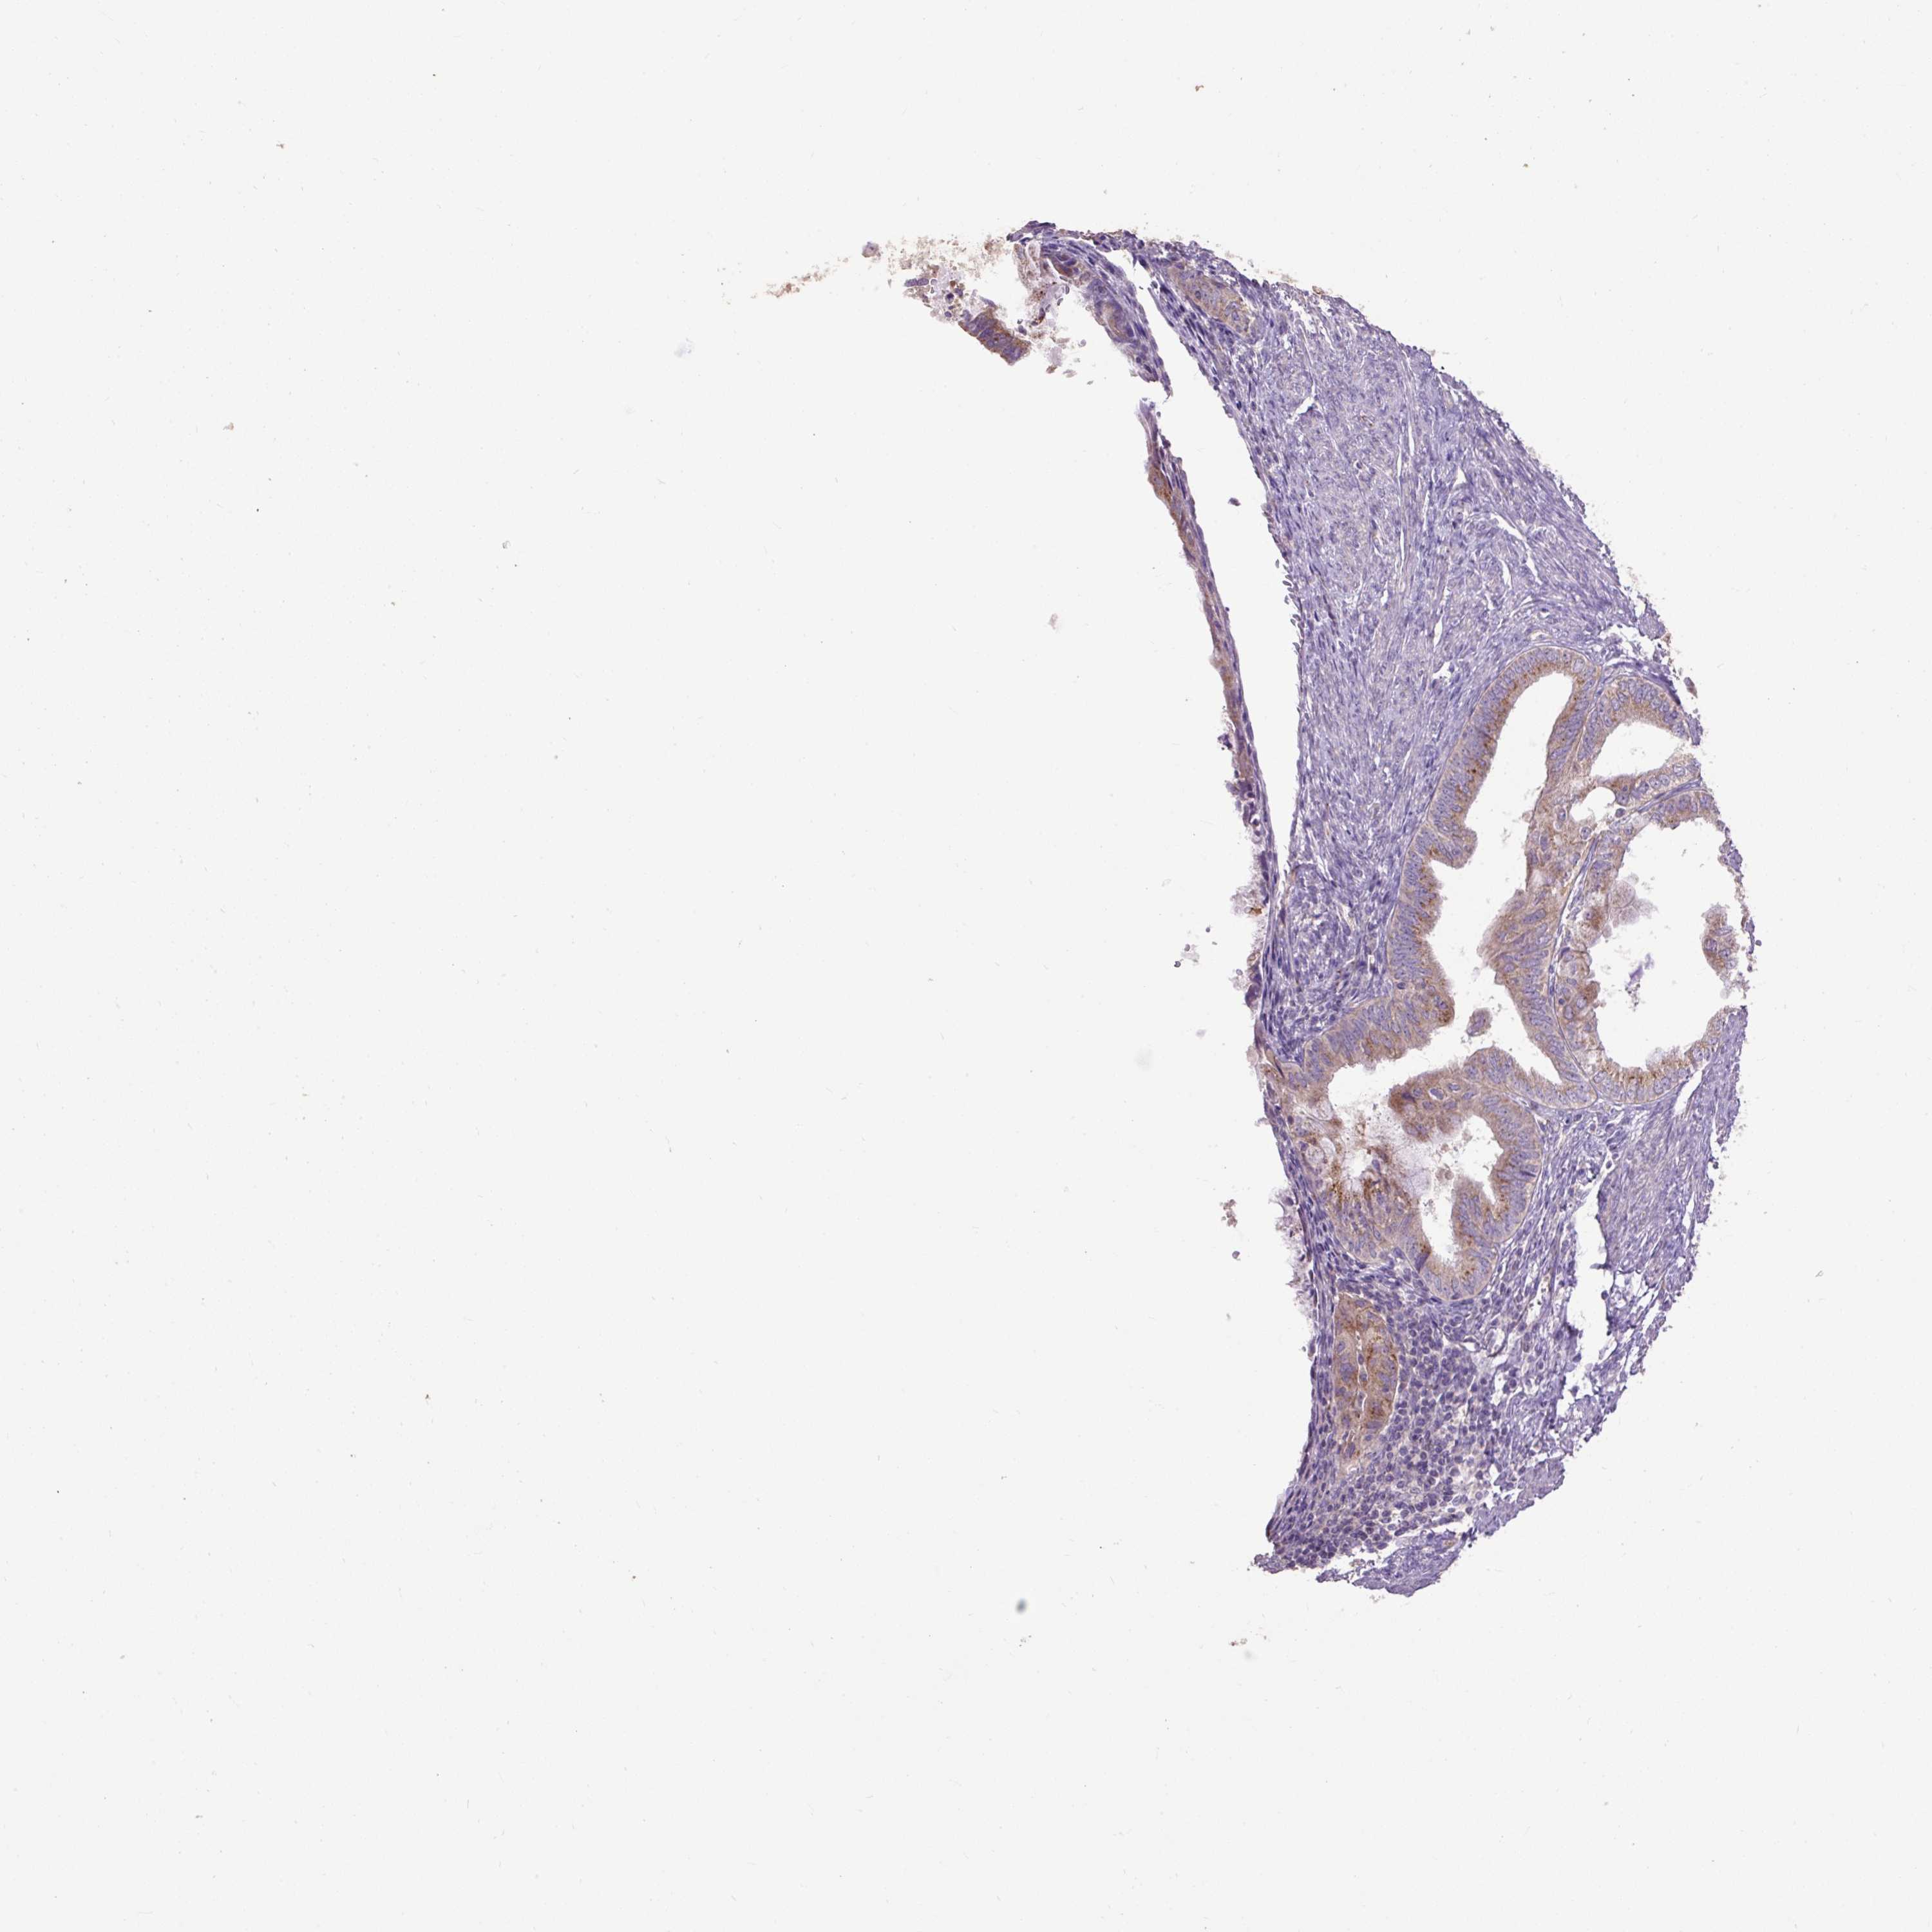

ENDOMETRIAL CANCER - Protein expressioni

A mouse-over function shows sample information and annotation data. Click on an image to view it in a full screen mode. Samples can be filtered based on level of antibody staining by selecting one or several of the following categories: high, medium, low and not detected. The assay and annotation is described here.

Note that samples used for immunohistochemistry by the Human Protein Atlas do not correspond to samples in the TCGA dataset.

Antibody stainingi

Antibody staining in the annotated cell types in the current human tissue is reported as not detected, low, medium, or high, based on conventional immunohistochemistry profiling in selected tissues. This score is based on the combination of the staining intensity and fraction of stained cells.

Each image is clickable and will lead to virtual microscopy that enables deeper exploration of all samples and also displays staining intensity scores, fraction scores and subcellular localization as well as patient and tissue information for each sample.

Antibody HPA054824

Staining

High

Medium

Low

Not detected

Intensity

Strong

Moderate

Weak

Negative

Quantity

>75%

75%-25%

<25%

None

Location

Nuclear

Cytoplasmic/membranous

Cytoplasmic/membranous,nuclear

Adenocarcinoma, NOS